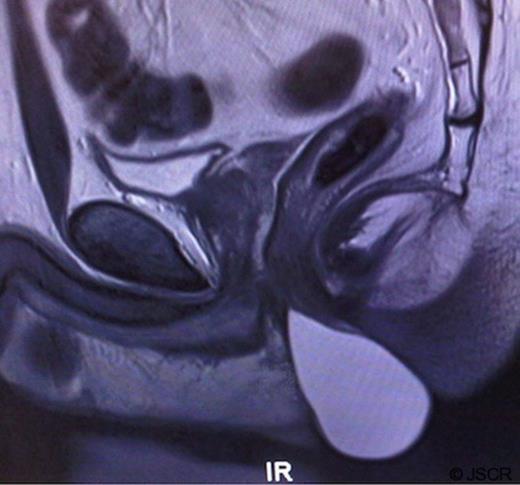

Further characterisation using magnetic resonance imaging (MRI) revealed a very well defined mass returning high signal on T2 weighted images suggesting fluid or proteinaceous contents. The lesion appeared to originate from between the internal and external anal sphincters, with the superior part of the lesion therefore lying in the intersphincteric plane and the lower part bulging out into the perineum. (Figure 1)

MRI of the pelvis showing a large cystic mass arising from the intersphincteric plane, lying anterior to the anal canal.

With the patient in the lithotomy position the lesion was excised in its entirety using careful dissection between the anal sphincters. Due to the size of the cavity left behind the skin was closed over a drain which was removed on the first post-operative day. The patient made a good recovery with no complications, including clinically intact anal sphincter function. To date there has been no recurrence. (Figure 2, Figure 3)